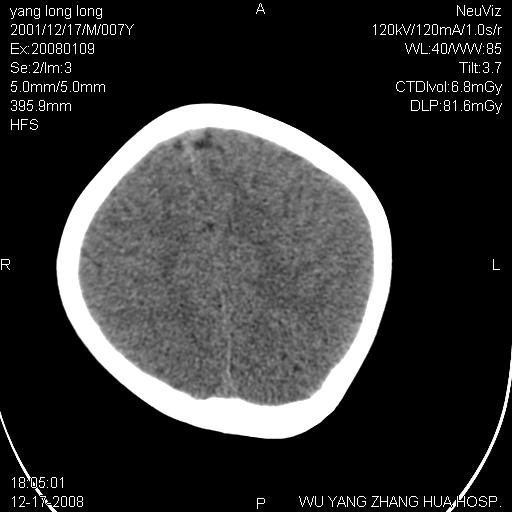

标题: PED1686:M7Y,头外伤,家人及自诉平时无任何不适。 [打印本页]

标题: PED1686:M7Y,头外伤,家人及自诉平时无任何不适。

考虑蛛网膜囊肿,请老师们看看多指导指导。

多考虑大枕大池。本例颅骨歪歪的,灶后枕骨似有膨胀征像(为蛛网膜囊肿征像),但整个左侧枕叶后方枕骨均有向后膨隆,所以暂不考虑蛛网膜囊肿。必要时随访

鉴别巨大枕大池与蛛网膜囊肿之间,倾向前者。